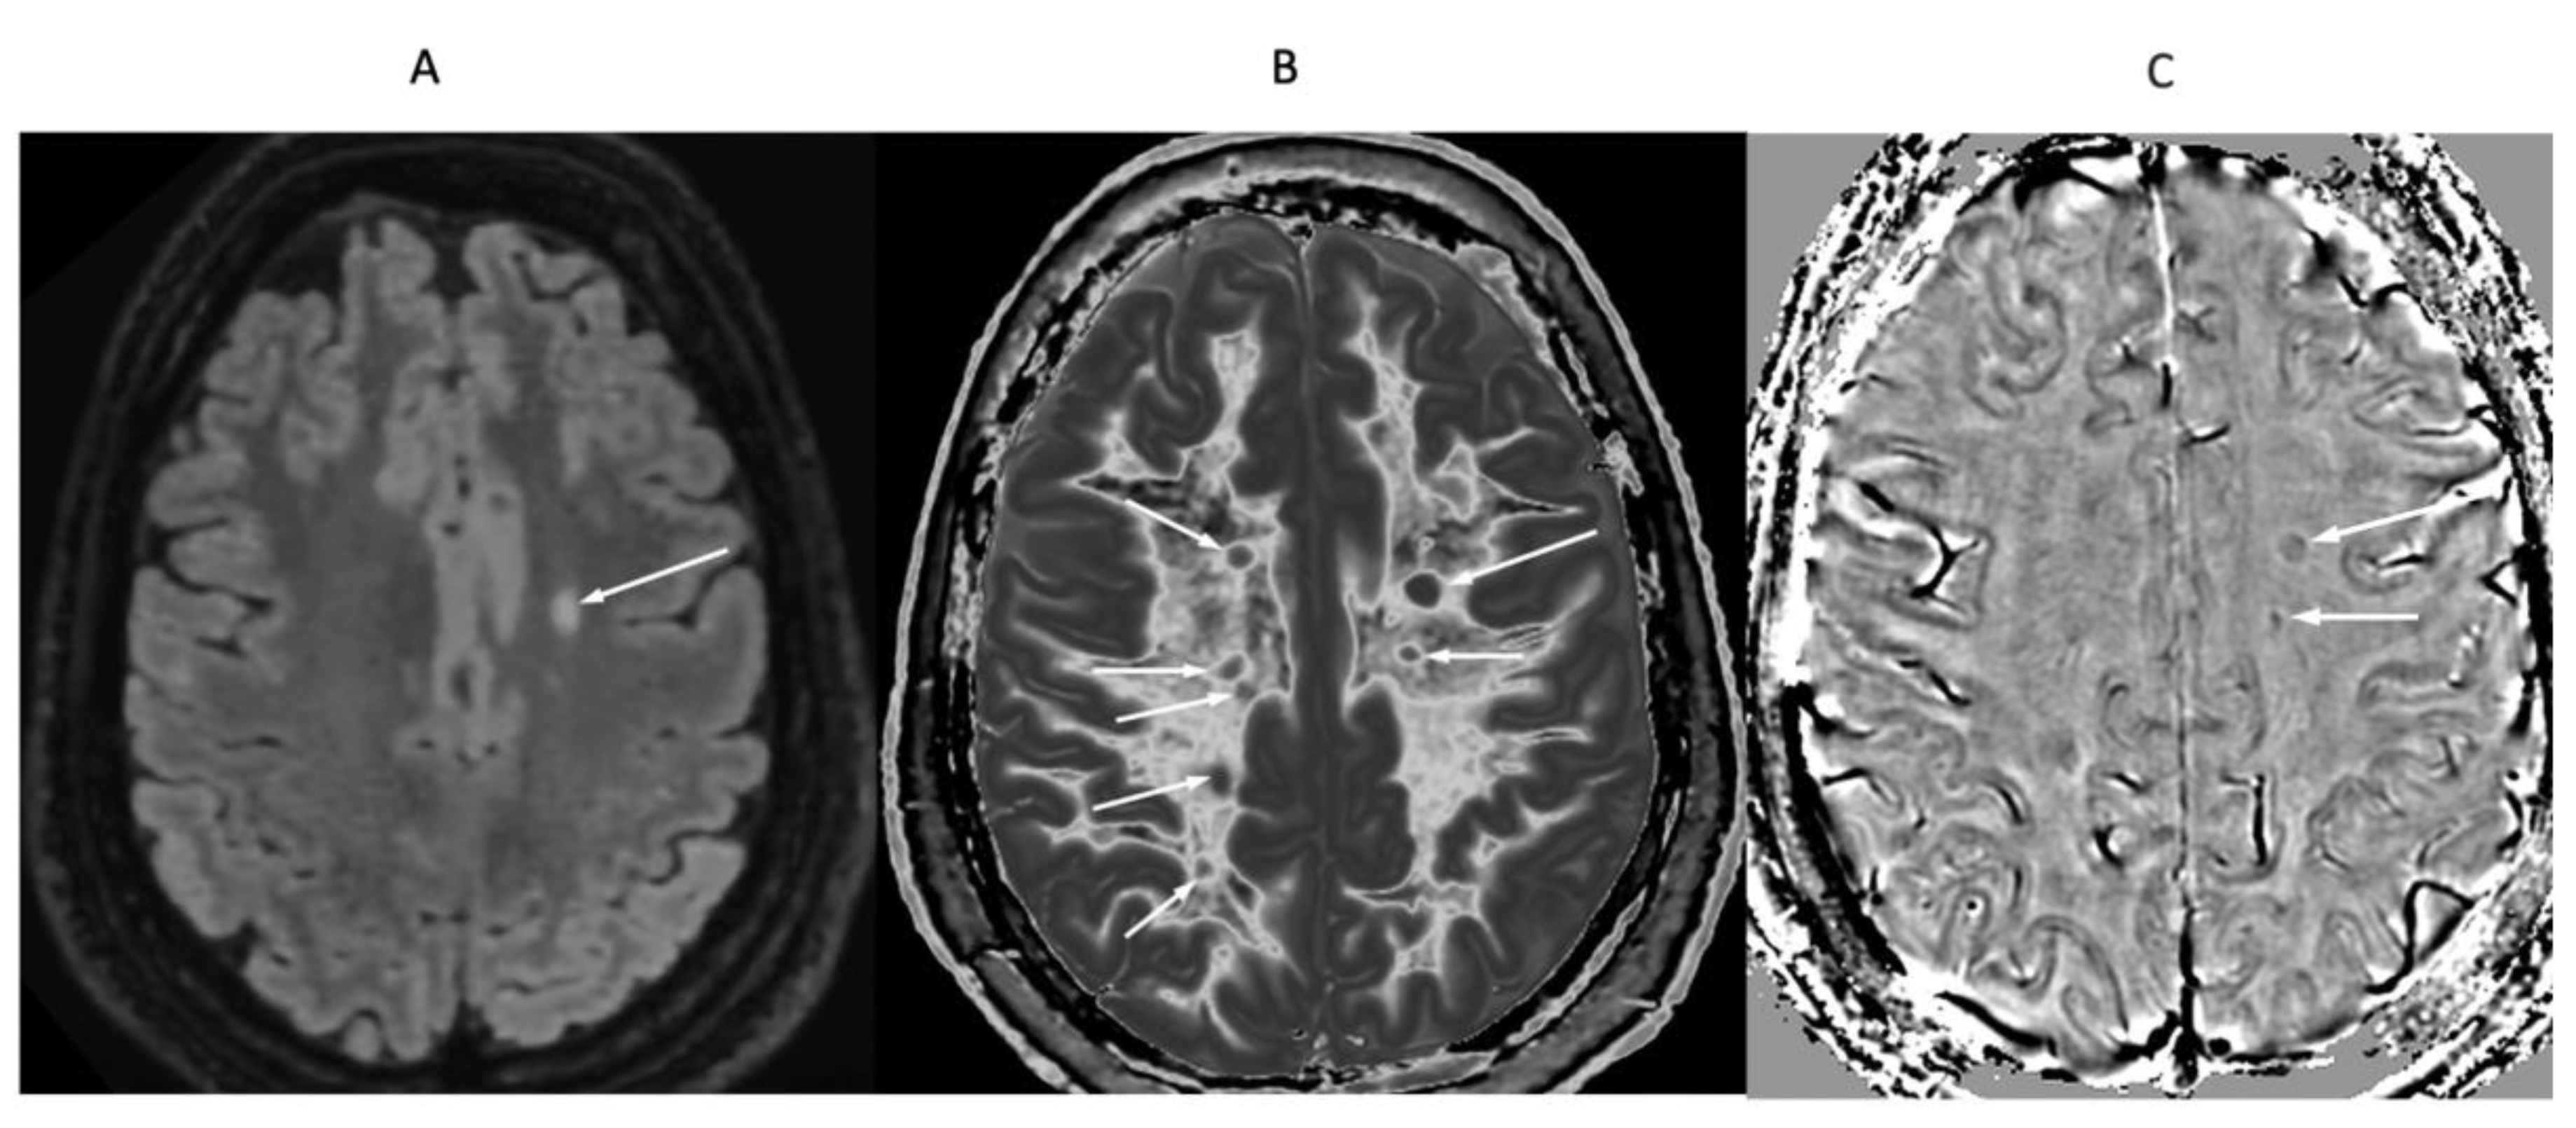

Figure 16.

32-year-old female with MS during a relapse. T

2-FLAIR (A), synthetic narrow mD dSIR (T

1-BLAIR) (B) and filtered gradient echo (C) images. On the T

2-FLAIR image (A), one lesion is seen (long arrow). The surrounding white matter appears normal. On the T

1-BLAIR image (B), the lesion shown on the T

2-FLAIR image is seen (long arrow) as well as six other lesions (short arrows). High signal boundaries around lesions are also seen in (B). Some of these lesions show paramagnetic rims on the filtered gradient echo image (arrows) in (C). In addition, most of the white matter in (B) is high signal corresponding to a high grade 4/5 whiteout sign [

1]. The whiteout sign is not seen on the T

2-FLAIR image (A).